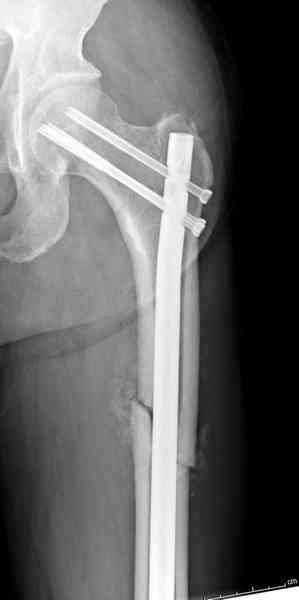

Здесь представлены снимки больного 65 лет, поступившего с диагнозом перелом

бедра после автоаварии.

В первый же день произведено антеградное штифтованием DePuy Trochanteric Nail.

На второй день (7) обнаружен пропущенный перелом,

сделаны Компьютерная Томограмма

и проведены шурурпы через и спереди штифта без удаления.

Послеоперационные снимки